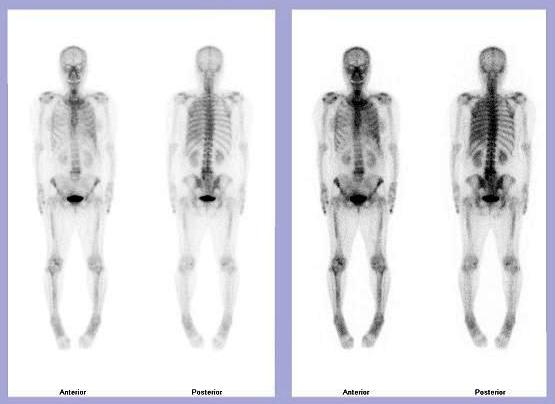

The patient is a 67-year-old female with a history of lung cancer.

There is mild uptake throughout the left lung likely related to a known left

pleural effusion.

There is increased tracer activity observed in the left aspects of the vertebral

bodies of L4 and L5.

Lesions in the vertebral bodies of L4 and L5 most likely representing

degenerative changes in correlation with the recent CT scan of the abdomen

pelvis showing no evidence of bony metastatic disease.